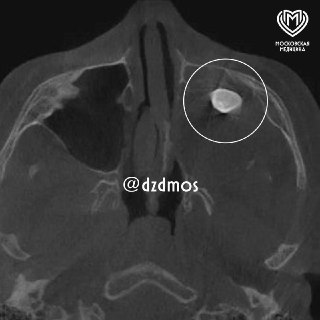

😨 В Москве у 15-летнего подростка в носу неожиданно пророс зуб.

Мальчик обратился к врачам с жалобами на заложенность носа и асимметрию лица. В гайморовой пазухе был найден сформированный зуб. После консультации в Филатовской детской больнице диагноз подтвердился — тератома, опухоль, содержащая различные ткани, включая зубы. Хирурги успешно удалили образование, и теперь парень снова дышит свободно, асимметрия лица исчезает.